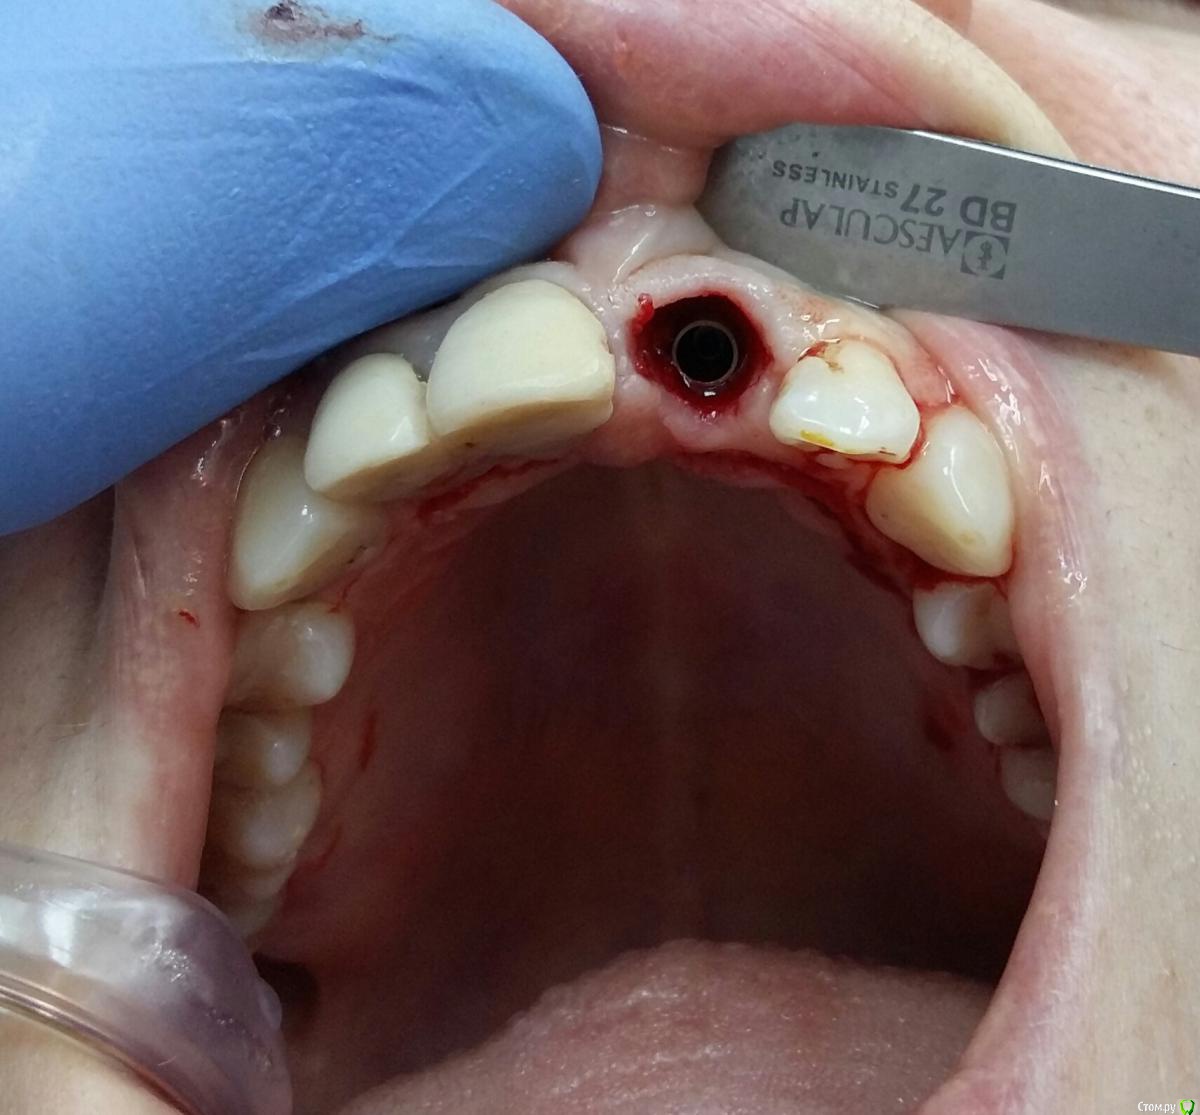

Kostoprav Опубликовано 8 ноября, 2017 Поделиться Опубликовано 8 ноября, 2017 заранее извиняюсь за качество фотографийдумал сделать все в один этап но торка ожидаемого не получил, поэтому пришлось накрыть винт випом.(материал osteobiol putyy) мне он очень понравиля ,удобный в работе. 17 Ссылка на комментарий

Kostoprav Опубликовано 8 ноября, 2017 Автор Поделиться Опубликовано 8 ноября, 2017 Торк был не достаточный для временной реставрации. Около 20. Я не рискнул.Срезы если найду выложу, хотя там ситуация стандартная ничего из ряда вон выходящего Ссылка на комментарий